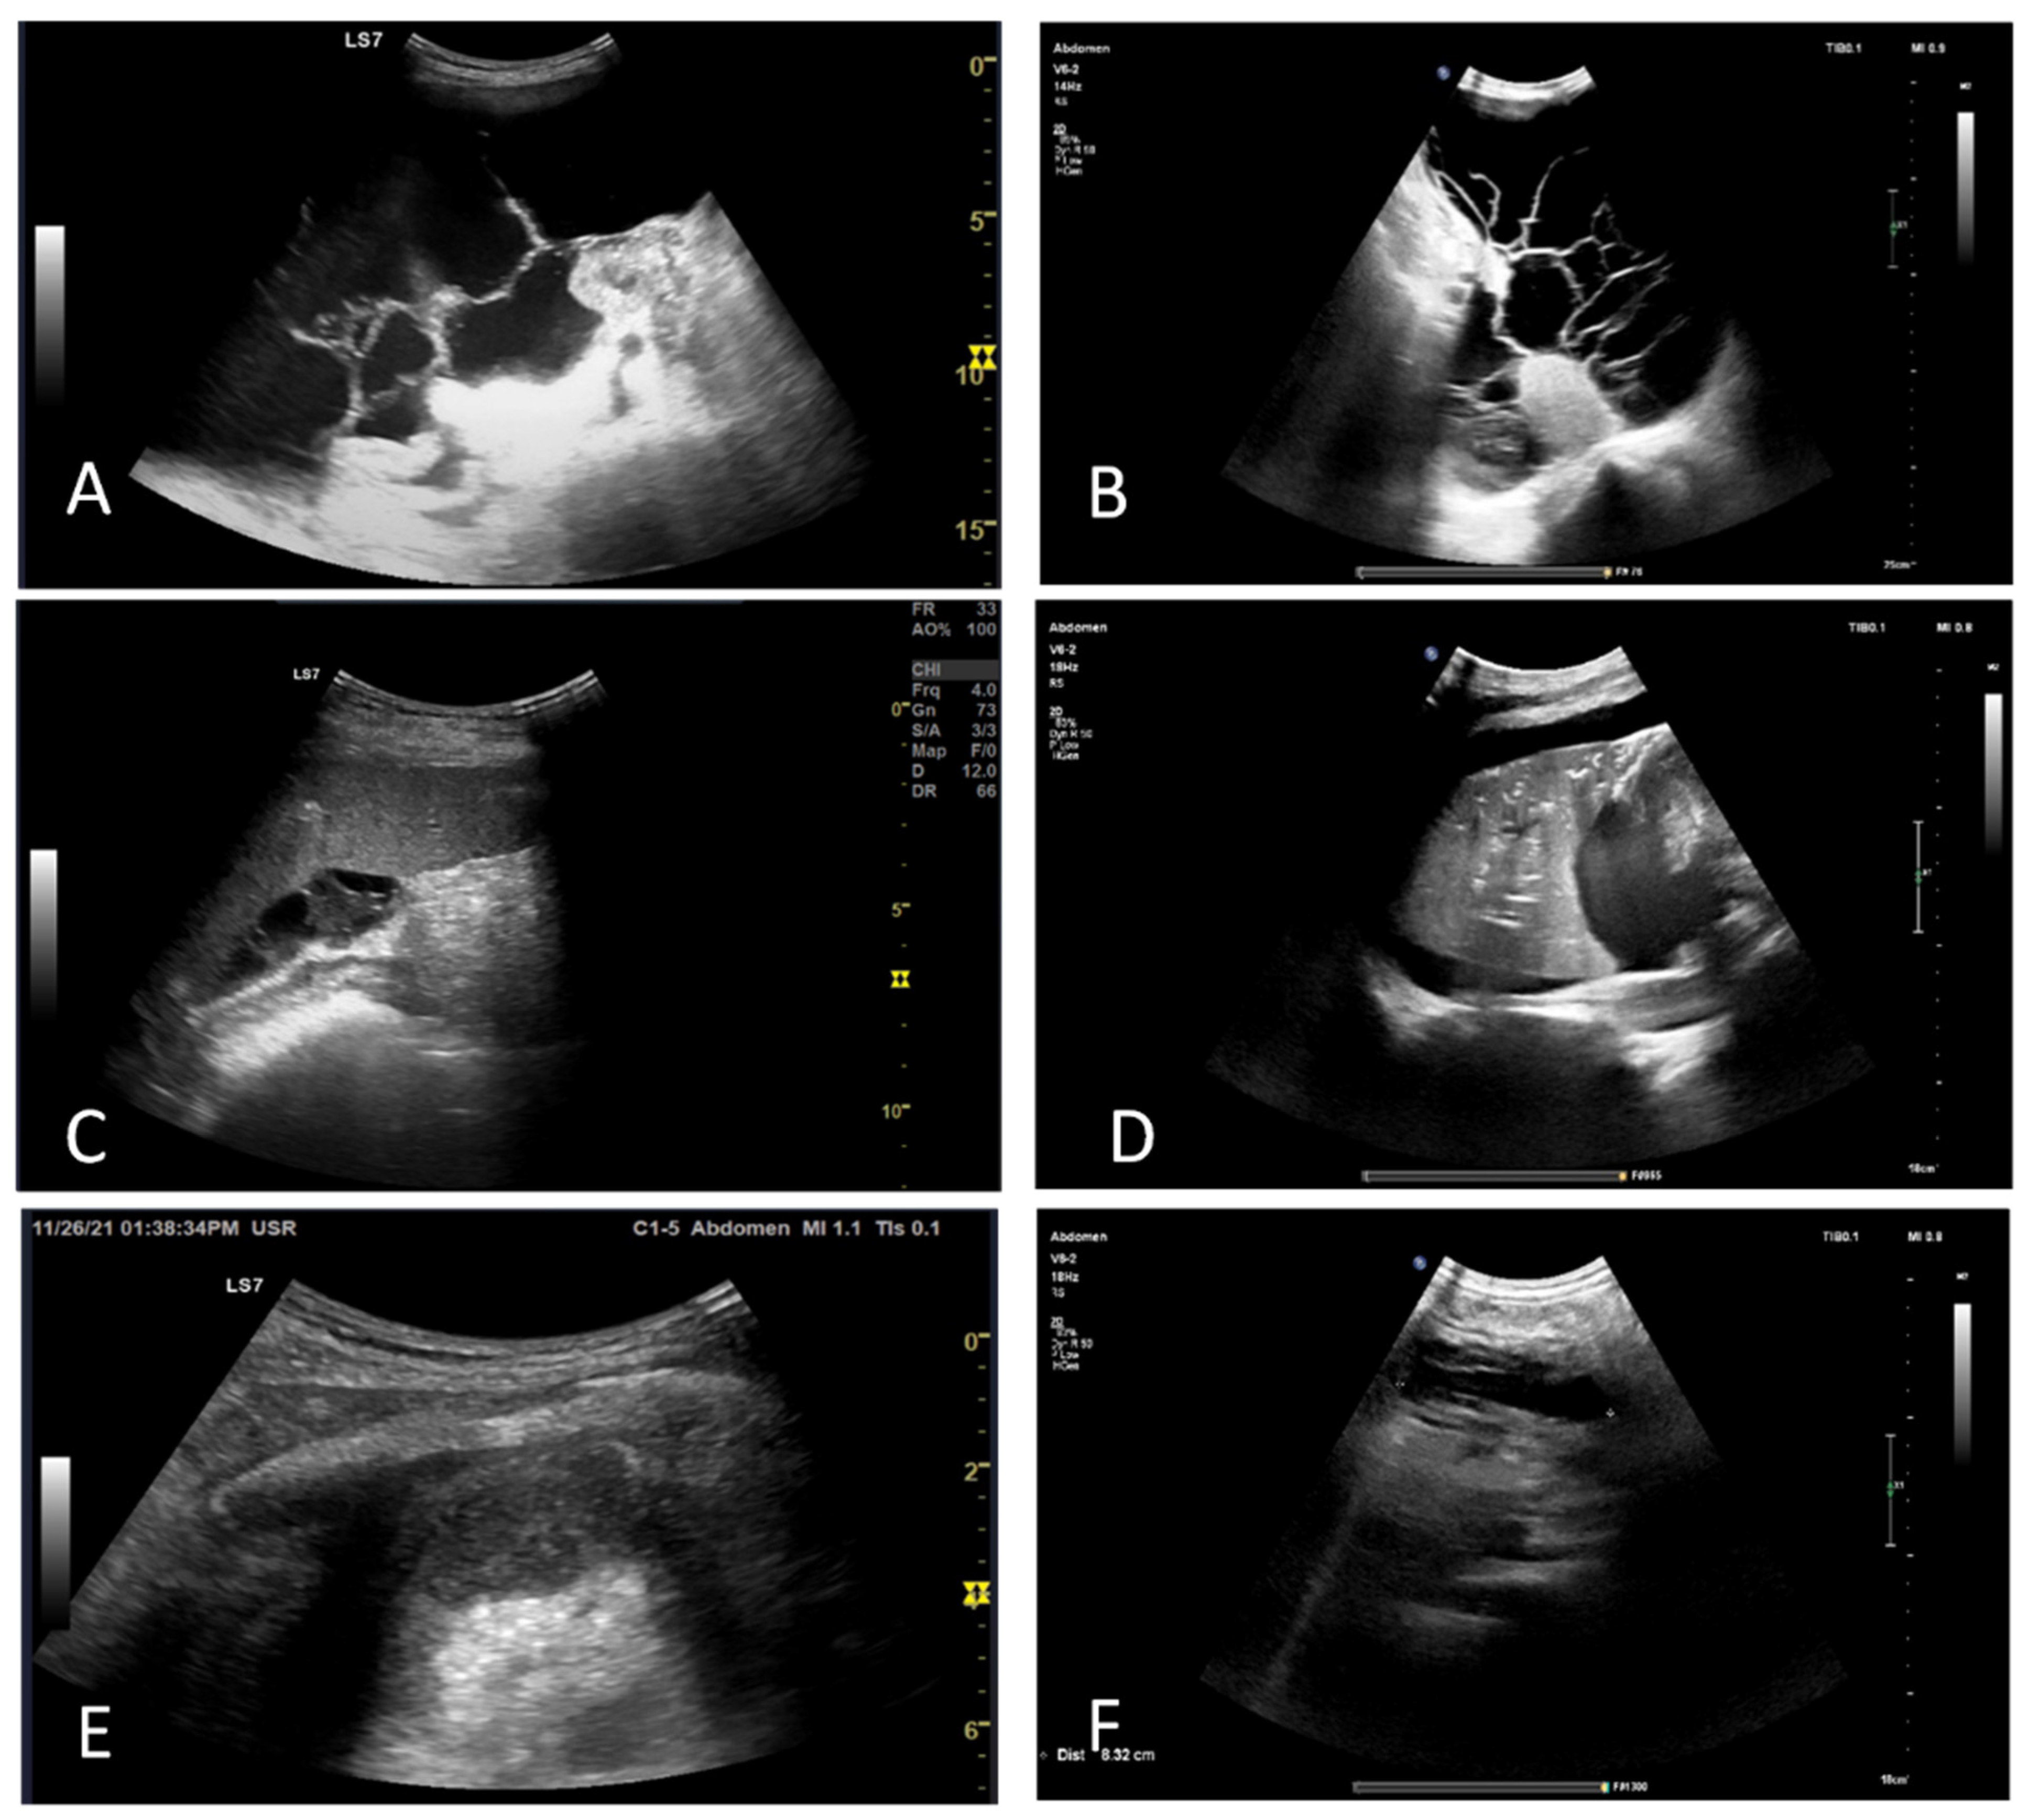

An abdominal US performed on day 16 and day 18 concluded that the patient developed necrotizing pancreatitis complicated by a pancreatic abscess. A CT scan confirmed the presence of the abscess (Figure 3B).

On day 30, arterial blood gas analysis showed severe ARDS with an arterial oxygen pressure-to-inspired fraction of oxygen (PaO2/FiO2) ratio of 50 and mixed respiratory and metabolic acidosis. Increasing inflammatory syndrome was accompanied by worsened renal function. A full blood count revealed severe anemia and thrombocytopenia. An abdominal US showed moderate ascites, retroperitoneal effusion, and necrotizing pancreatitis (Figure 4B). Transthoracic echocardiography and lung US were notable for mild tricuspid and severe mitral regurgitation, mild pulmonary hypertension, an ejection fraction within normal limits, large pleural effusions, and atelectasis (Figure 4C–E). Diagnostic paracentesis was performed for cultures (Table 2). Following the convulsive episode, a head CT scan was performed, and areas of recent ischemia were discovered in the right postero-superior frontal lobe, postero-superior parietal lobe bilaterally, and the right posterior occipital lobe. Heart US was performed, which ruled out endocarditis.

Figure 4. Abdominal and thoracic ultrasound in evolution. (A,B): Peritoneal effusion with septa. (C):Perisplenic cloasonated peritoneal effusion. (D): Pleural effusion of the inferior lung lobe, with air bronchograms. (E,F): Left subphrenic effusion, showing deep enhancement, suggestive of infection (abscess).